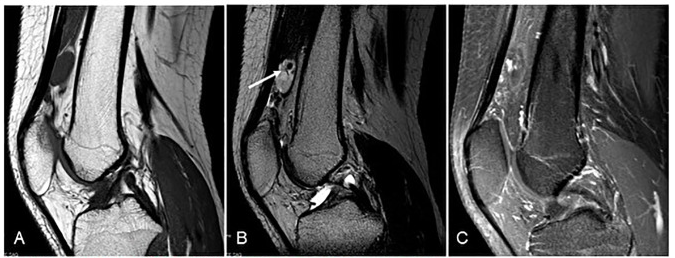

3.2 RM — Estándar

- T1: iso/hipointensa (a veces heterogénea).

- T2/STIR: típicamente hiperintensa y lobulada.

- Post-contraste: realce marcado (difuso o septal).

- Diferencial clave: en PVNS/TGCT domina la hemosiderina (blooming en gradiente), algo que aquí no debería ser el patrón principal.

- Puede haber flow-voids si componente de alto flujo (menos frecuente).